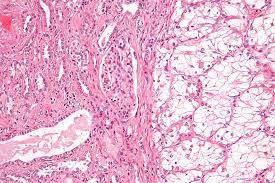

Iesalnieks i1, trupka a, raab m, glockzin g, woenckhaus m, schlitt hj, agha a. The development of the krukenberg tumor is not from general gastric cancer, but it is a specific form of cancerous growth arises from signet ring cell carcinoma of the stomach and spread to adenocarcinoma of the ovary. metastasis is a pathogenic agent's spread from an initial or primary site to a different or secondary site within the host's body; Stage iv means cancer that has spread widely or cancer that has metastasised. Clear cell renal cell carcinoma is named after how the. Dua jenis tumor yang paling sering ditemukan pada colorectal adalah adenoma atau adenomatous polip dan adenocarcinoma. Clear cell renal cell carcinoma is also called conventional renal cell carcinoma. Hepatocellular carcinoma (hcc) adalah keganasan primer dari hati dan terjadi terutama pada pasien dengan penyakit hati kronis dan sirosis. Choriocarcinoma is a malignancy of placental origin.it is an aggressive form of cancer originating from the trophoblast cells in the placenta. Metastatic liver tumors are largely silent until the disease is well advanced.2 patients with metastatic colorectal tumors frequently die of hepatic failure due to liver metastasis. We report one case of villoglandular papillary adenocarcinoma (vgpa) of the uterine cervix with lymph node metastasis and reviewed the clinicopathological features of six other cases reported in the literature. Stage 0 means the presence of a small carcinoma in situ that has not spread. The proportion of pathologic lymph node metastasis among scirrhous carcinomas is significantly higher than that among carcinomas of other histological types 2.

The proportion of pathologic lymph node metastasis among scirrhous carcinomas is significantly higher than that among carcinomas of other histological types 2. Hepatocellular carcinoma (hcc) adalah keganasan primer dari hati dan terjadi terutama pada pasien dengan penyakit hati kronis dan sirosis. Sclc biasanya lebih agresif dari nsclc dan sering terdapat metastasis jauh, terutama ke tulang, hepar, kelenjar adrenal, perikardium, otak, dan medula spinalis. Dua jenis tumor yang paling sering ditemukan pada colorectal adalah adenoma atau adenomatous polip dan adenocarcinoma. Clear cell renal cell carcinoma is also called conventional renal cell carcinoma.